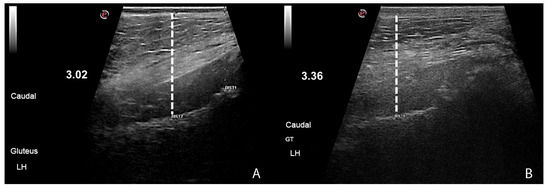

2.5. Blood Tests and Muscle Size Evaluations

3.3. Blood Tests and Muscle Evaluations